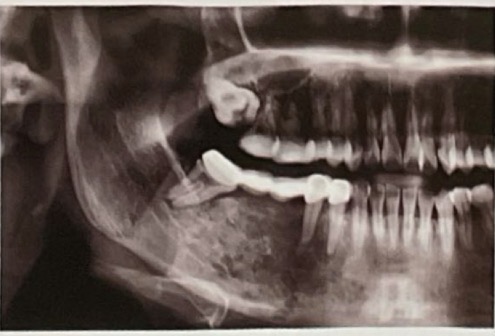

CHẨN ĐOÁN ?

HOẠI TỬ XƯƠNG HÀM sau xạ trị

CHẨN ĐOÁN?